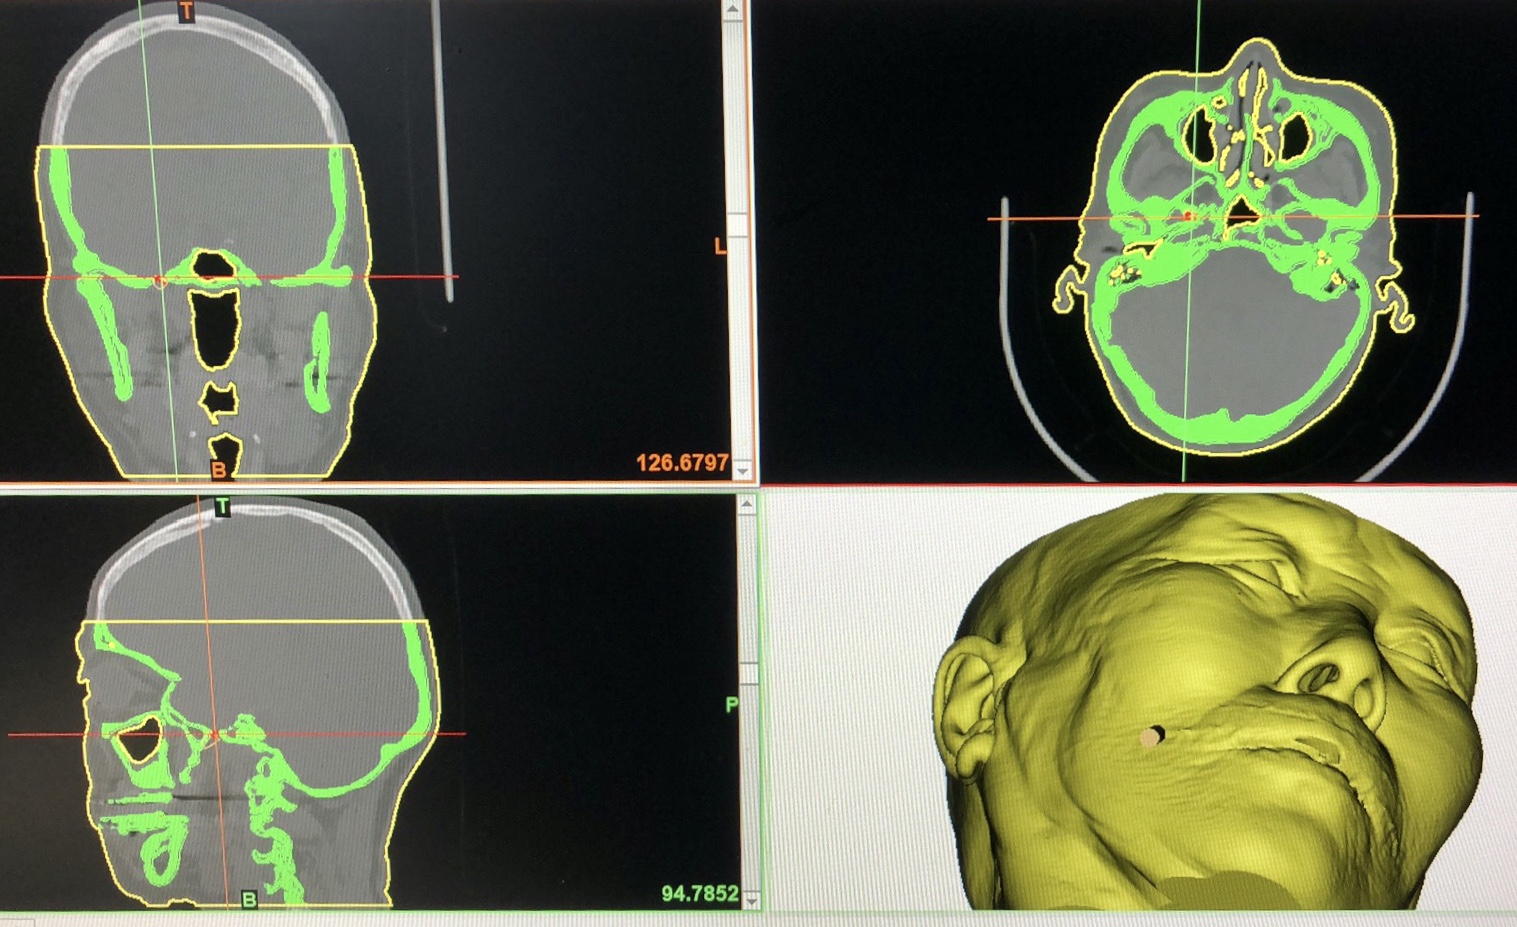

三叉神经节球囊压迫术是指通过在三叉神经半月神经节的局部置入机械球囊,压迫感觉神经节,导致神经节组织局部发生坏死,阻断疼痛信号向脑内传导,从而达到治疗神经痛的目的。技术的关键点在于将球囊精准而安全地置入脑内神经节的位置,对手术的精准度有一定的要求。虽然在临床上现有的导航技术也可以满足精准的要求,但导航设备昂贵、医疗花费较高,考虑到袁阿姨家庭经济实力,决定采用性价比较高的导引板导引技术来实现靠高端导航设备所能完成的手术精准度。首先,我们通过颅脑CT扫描,在计算机中重建袁阿姨头面部三维模型,手术模拟穿刺点和穿刺过程,依据手术模拟结果在计算机中设计虚拟穿刺导引板,模拟在穿刺导引板引导下穿刺针位置、方向和深度,为手术提供关键信息。最后,我们利用3D打印技术打印出符合手术要求精度的实物导引板。